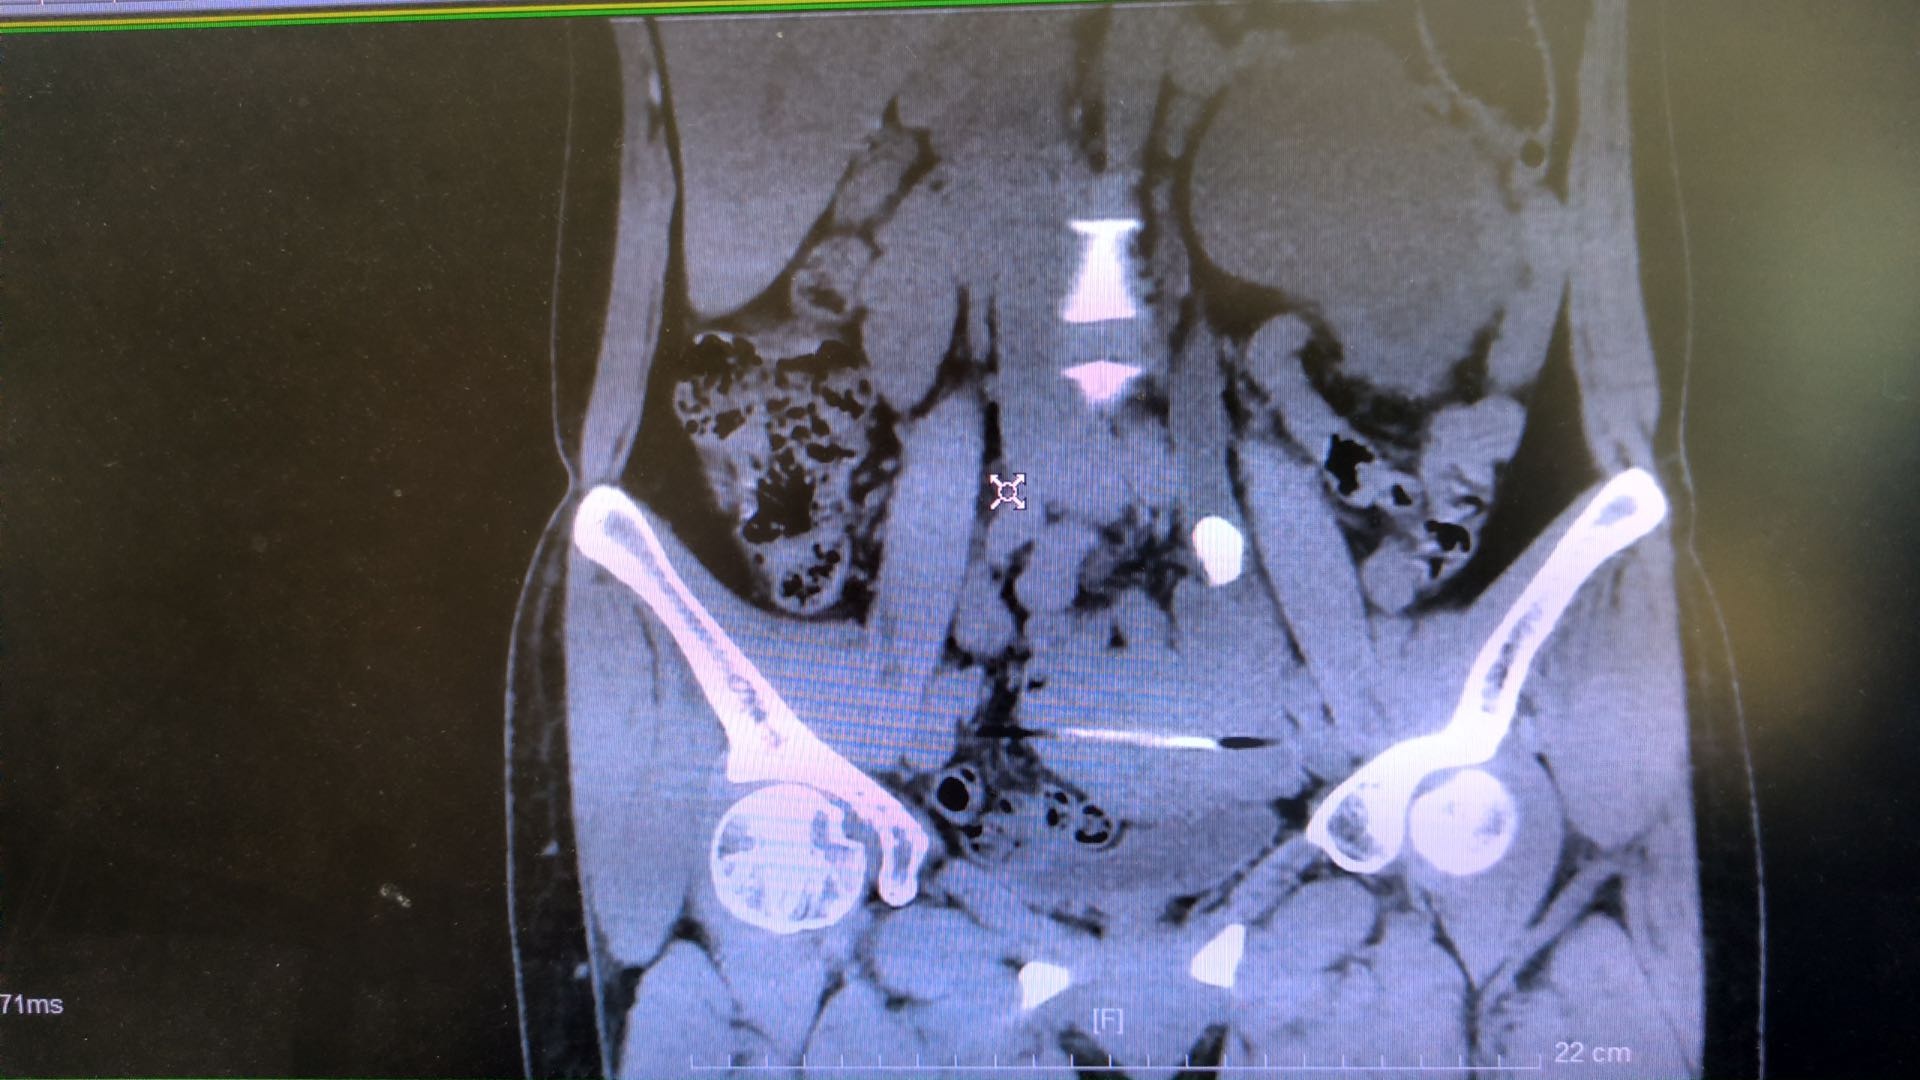

41岁的王女士平时经常腰部酸胀不适,腰痛反复发作,严重影响生活质量。11月25日上午,王女士左侧腰部剧烈疼痛,并持续两天,入住武汉市第五医院泌尿外科,经医生诊断为输尿管结石伴肾脏重度积水,石头直径超过2CM。考虑到王女士结石较大,且肾脏重度积水患者肾皮质较薄,使用传统输尿管镜碎石手术会造成肾内压力较大,容易产生肾破裂风险,武汉市第五医院泌尿外科主任李颢决定使用组合镜进行碎石并取石,相较于传统输尿管镜,组合镜优势在于碎石与取石可同步完成,微创近无创,并且大大降低重度肾积水患者碎石手术中因肾盂压力过高导致肾破裂的风险。

入院后第二天泌尿外科团队对王女士进行组合镜下输尿管碎石取石术,带有负压的组合镜在碎石过程中,通过持续的负压吸引将小结石同时吸出,大大减少了结石残留及移位进入肾脏的风险,同时也提高了取石效率。手术过程顺利,仅用20多分钟便顺利完成。术后第二天王女士便康复出院,随访结果腰部已无疼痛。

泌尿外科主任李颢介绍,组合镜是一种既可以碎石,又同步清石的治疗上尿路结石的新装备。组合输尿管硬镜经人体自然腔道逆行可视下进入人体的输尿管,运用钬激光把结石击碎呈粉末状,再通过负压鞘将其“吸”出体外,弥补了传统治疗方法“只碎石不排石”的弊端;还可根据手术操作过程中的需要,随时通过调节阀主动控制腔道内压力,防止术中腔道高压带来的系列风险,实现安全治疗。同时,如果肾内有结石或者输尿管较大残石进入肾盂、肾盏内,可以留置组合输尿管镜外鞘,一期置入输尿管软镜击碎肾内结石。